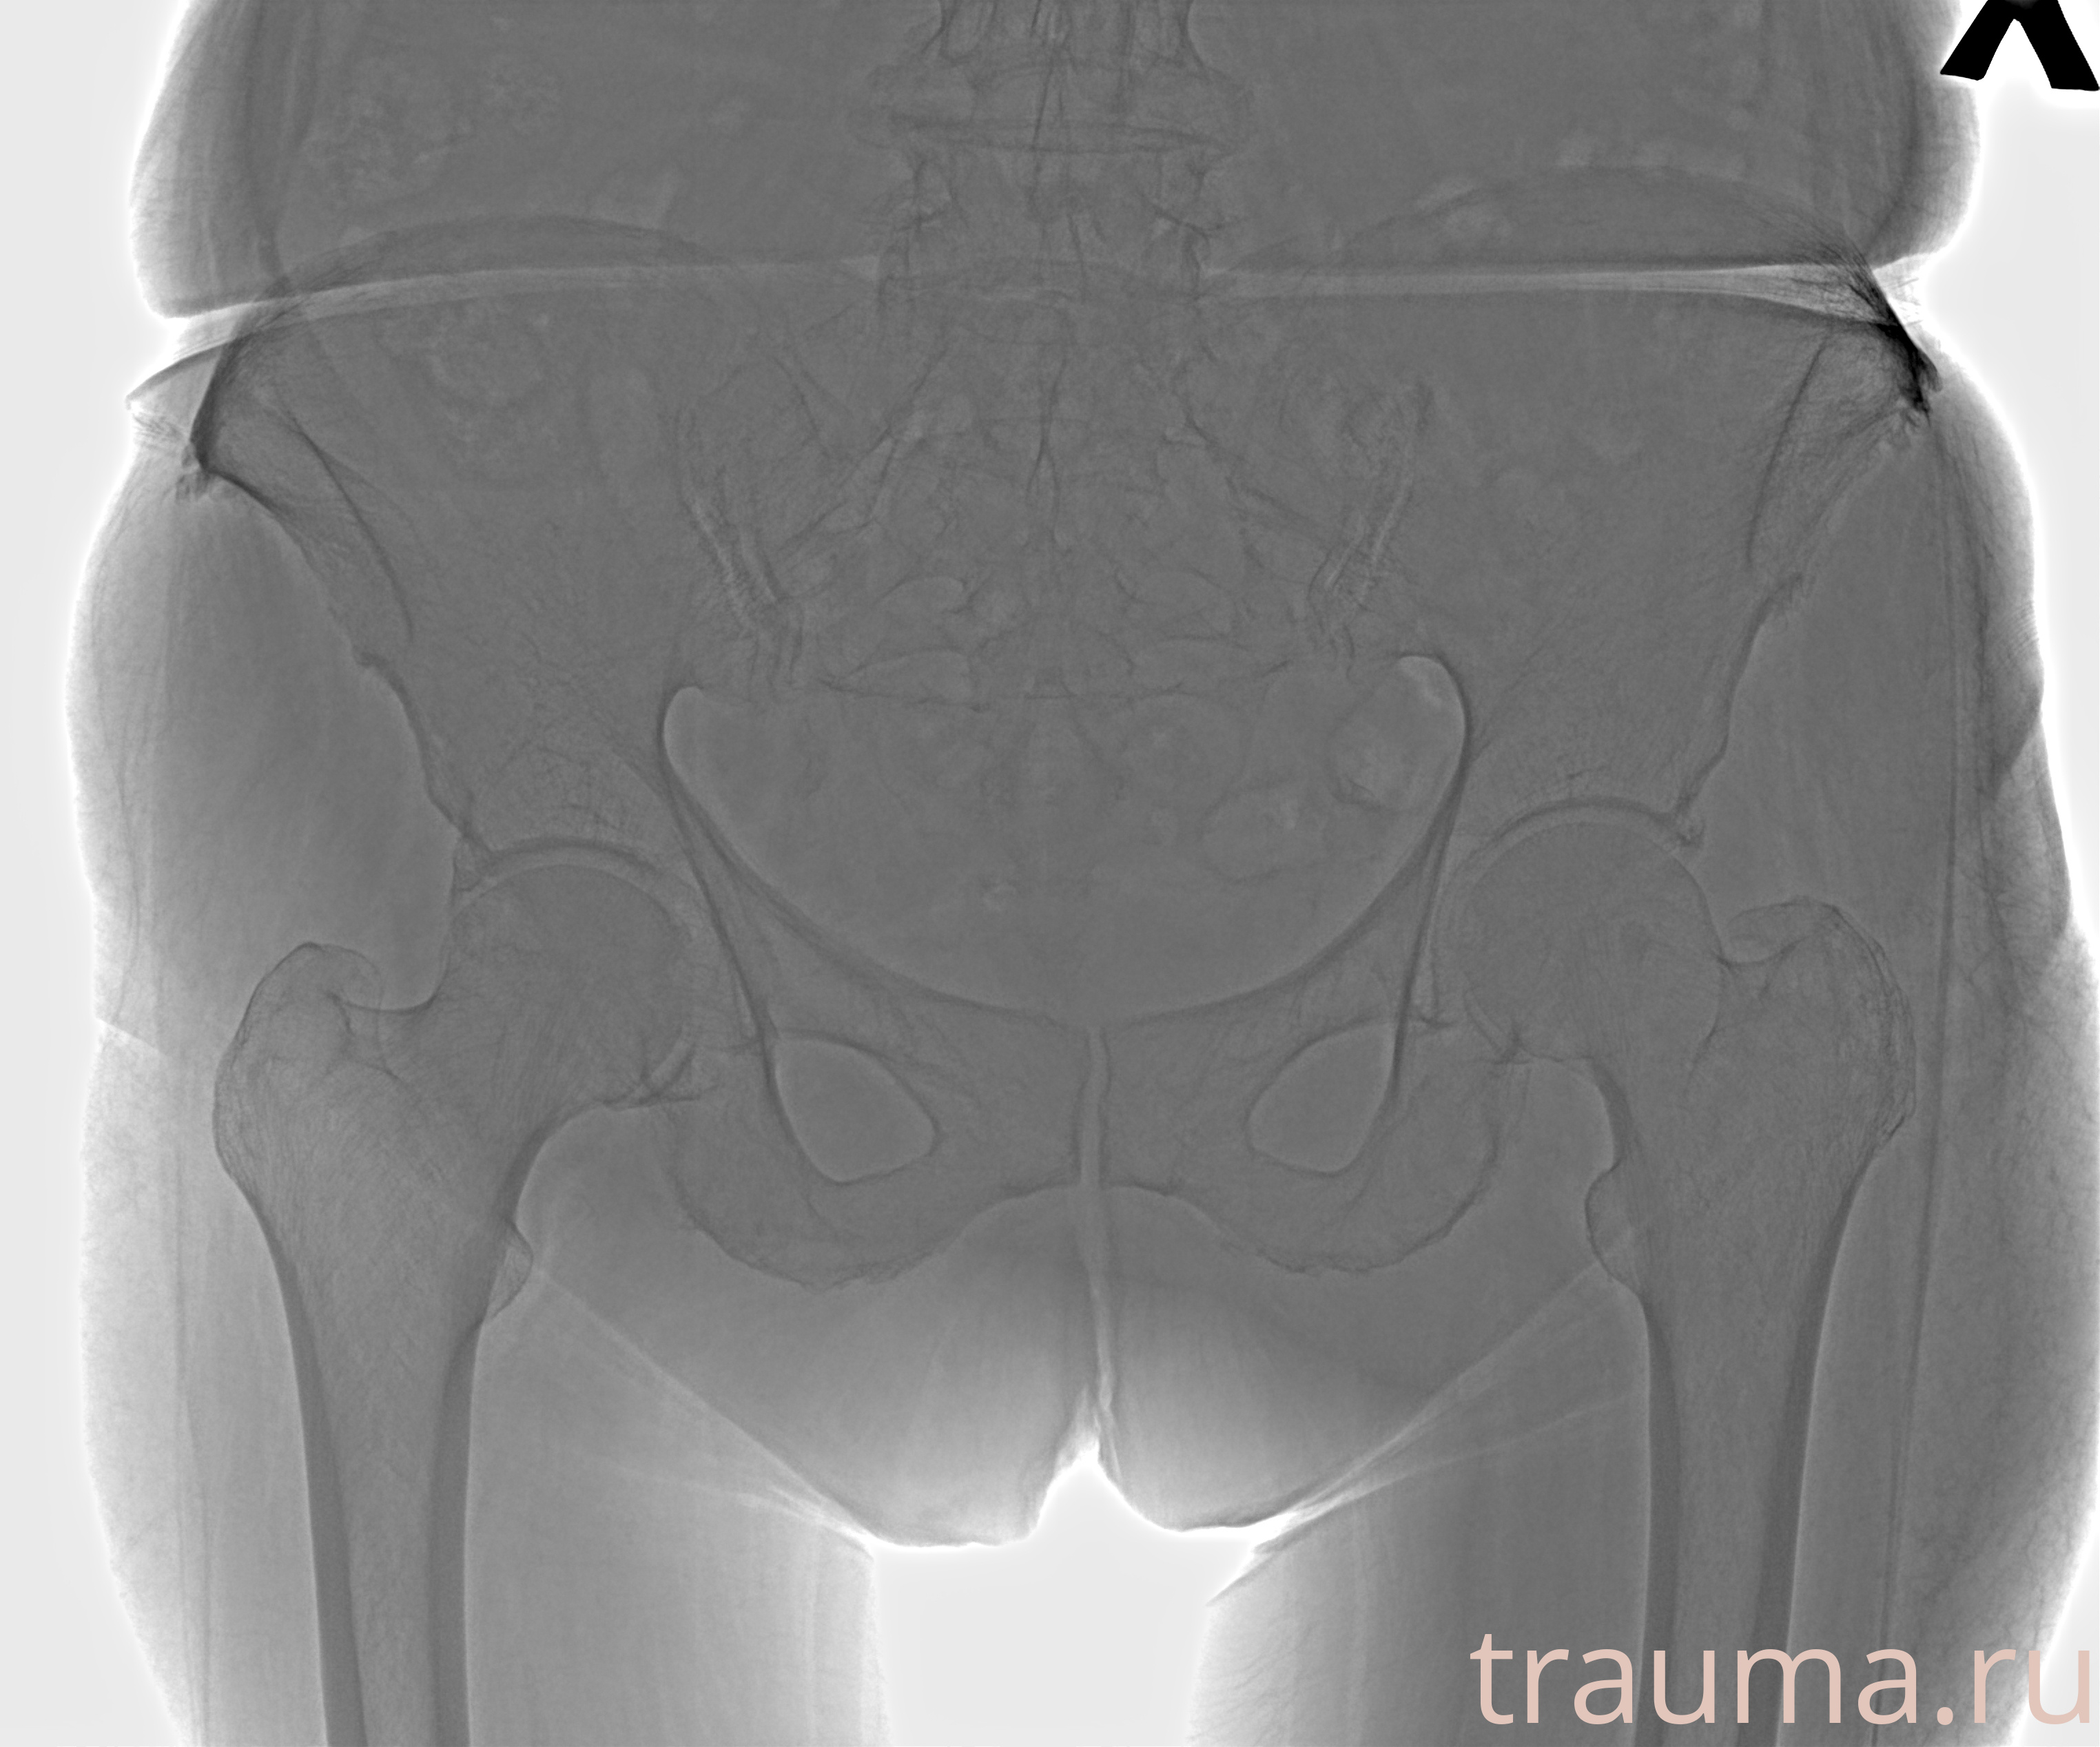

Рентгенограммы

Рентген на дому: по вашему адресу приезжает врач-рентгенолог, травматолог-ортопед с мобильным рентгеновским аппаратом, проводит диагностику травмы или заболевания, делает необходимые рентгенограммы, дает рекомендации по дальнейшему лечению. Получить качественные снимки в домашних условиях возможно благодаря уникальной методике, разработанной МосРентген Центром для института  Склифосовского